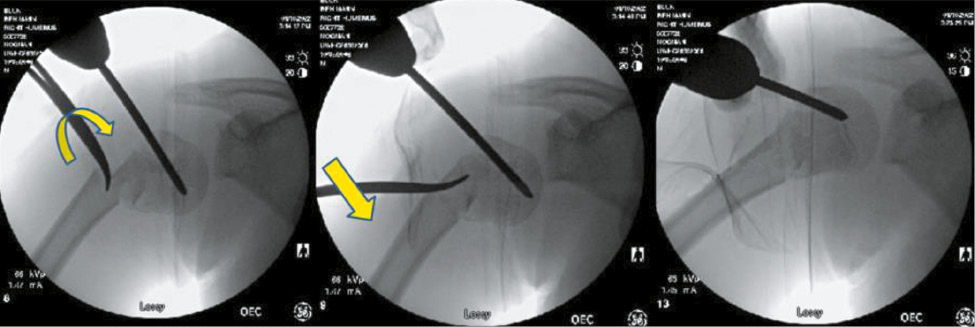

As a result of this issue, if initial attempts at closed reduction fail, a Schanz pin can be placed into the humeral head to hold it in place while the distal fragment is manipulated. A percutaneous incision is made 1-2 fingerbreadths lateral to the acromion with blunt dissection carried to the level of the capsule. Using fluoroscopic guidance, a 4.5 or 6 mm Schanz pin (size may be adjusted depending on the size of the patient) is placed through a drill guide into the humeral head roughly parallel to the physis, advancing at low rotations per minute to avoid undue torque on the proximal fragment (Figure 6). Once secure, the pin can then be used as a joystick to aid in reduction.

Figure 6. A Schanz pin is slowly advanced into the proximal humerus, and a screw guide is used to prevent soft tissue injury.

In the process of performing a closed reduction with or without proximal pin stabilization fixation, it is common to find the fracture alignment improved in angulation and cortical contact. If closed reduction is unsuccessful at achieving acceptable alignment, prior to open reduction, one can use a modification of the Kapandji method to reduce the fracture. A stout k-wire or surgical instrument can be percutaneously placed into the fracture site and leverage the fracture fragments into place. We prefer to use a blunt hemostat, as it can be used to gain access to the fracture site safely, and the curved nature can hook the cortex of the “distal bone” and translate to the “proximal bone” to align. Prior to leveraging the bone, one can open the tines of the hemostat when in the fracture site which may prevent comminution during reduction (Figure 7).

Figure 7. The curved portion of the tonsil is then used in a Kapandji-type or shoehorn maneuver: inserted into the intramedullary space, rotated, and used to lever the fracture fragments into a reduced position.